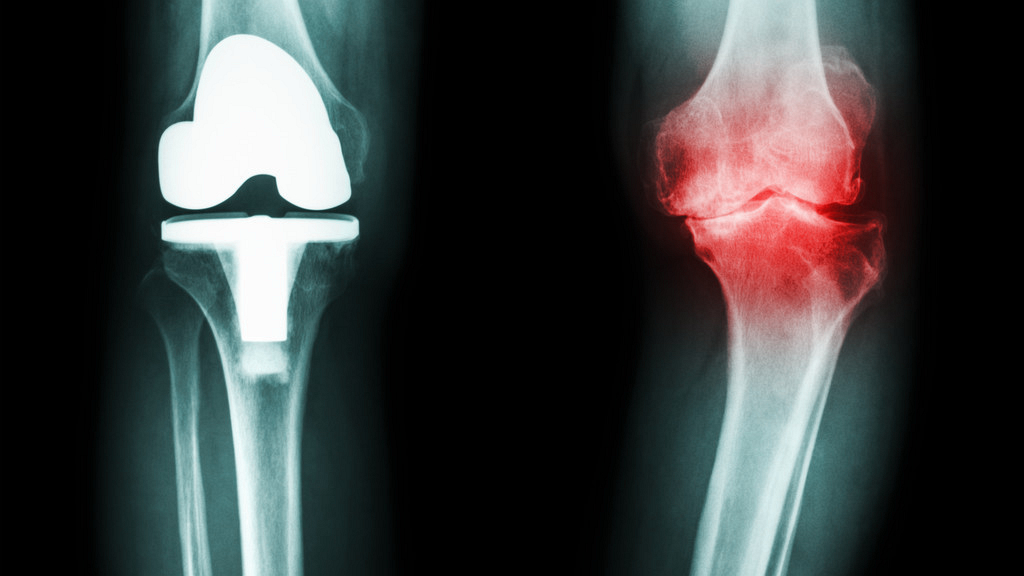

其次,要想确定感染,还要借助辅助检查,就是所谓的客观证据。

如果我们怀疑感染的话会对关节做一些初步的检查,比如说x光片,看看骨头有没有溶解的现象;抽血查白细胞,血常规,血沉以及降钙素原等各种炎症指标。ECT全身骨扫描也是比较常用的一些方法。另外还有一个在各种指标都不能确认的情况下,我们需要做一些关节穿刺,看一下关节液的一些常规,生化以及细菌学培养的结果来辅助我们做一些判断。